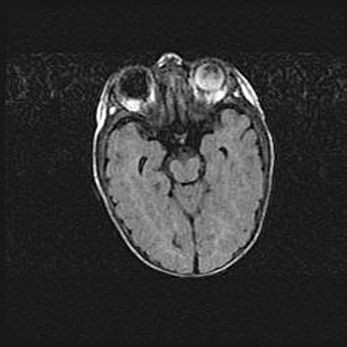

Сообщающаяся гидроцефалия. Кистозная энцефаломаляция головного мозга.

Возраст: 3 месяца 4 дня

Вес: 3100 г

Пол: женский

Окружность головы: 34 см

Срок гестации: 31 неделя

Кистозная энцефаломаляция головного мозга - одна из форм поражения головного мозга в детском возрасте. Характеризуется возникновением множественных и распространённых кист в коре, белом веществе и подкорковых образованиях головного мозга у плодов, новорождённых и детей раннего возраста. Развитие кистозной энцефаломаляции связано с внутриутробной асфиксией и гипотонией, родовой травмой, тромбозом синусов, пороками развития сосудов, инфекциями, сепсисом и другими причинами. Наиболее значимые инфекционные агенты: вирусы простого герпеса, цитомегалии, краснухи, токсоплазмы, энтеробактерии, золотистый стафилококк и другие.